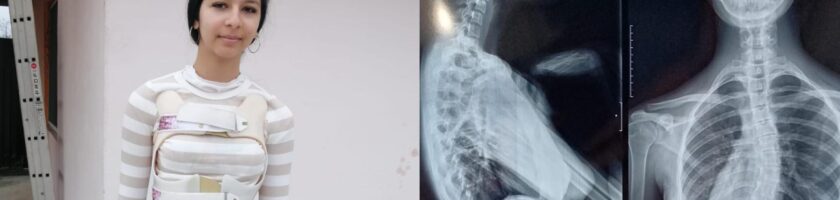

Erika Maria Stîngaciu, o adolescentă de doar 15 ani din Râmnicu Vâlcea, se confruntă cu un diagnostic sever de scolioză dorsolombară progresivă, o afecțiune care îi modifică zilnic postura și îi afectează profund calitatea vieții.

A urmat zilnic ședințe de kinetoterapie, a purtat un corset rigid tip Cheneau timp de 23 de ore din 24 și a trecut prin multiple consultații și investigații în centre medicale din țară. În ciuda tuturor eforturilor, evoluția a continuat, iar în februarie 2026, în urma unui nou control, medicii au confirmat caracterul progresiv al scoliozei și necesitatea unei intervenții chirurgicale.

În prezent, Erika continuă să poarte corsetul zilnic și să urmeze terapii, însă acestea nu mai pot opri evoluția deformării coloanei. Singura soluție rămasă este intervenția chirurgicală, care îi poate reda șansa la o viață fără durere și fără limitările actuale.